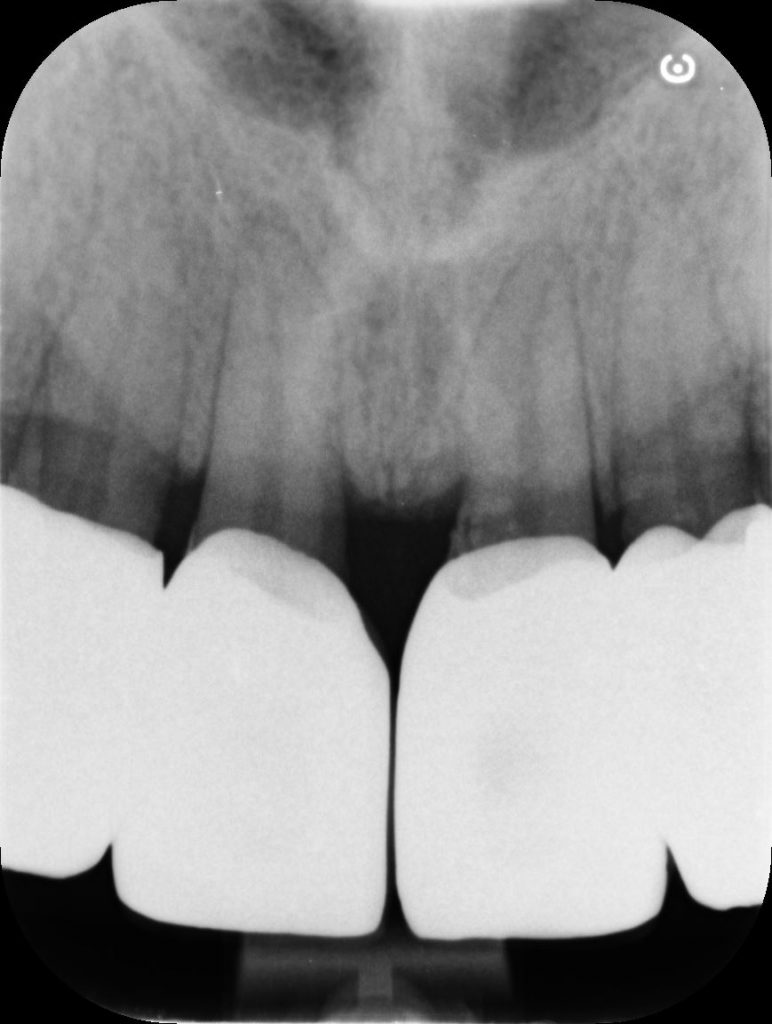

RX frontal view